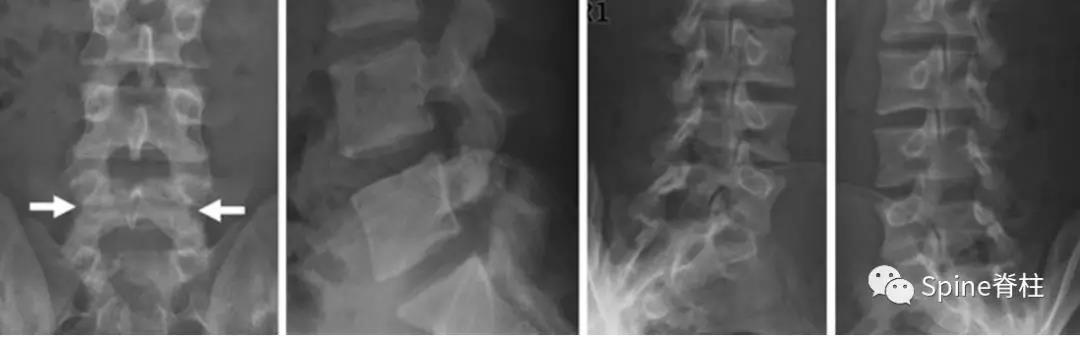

图:起始CT提示L5左侧峡部裂(双箭头),起始CT检查后2个月复查可见出现右侧椎弓根裂(单箭头),4个月复查可见椎弓根裂愈合(单箭头)

图:6个月复查可见右侧椎弓根裂已愈合(单箭头),但出现右侧峡部裂(双箭头)